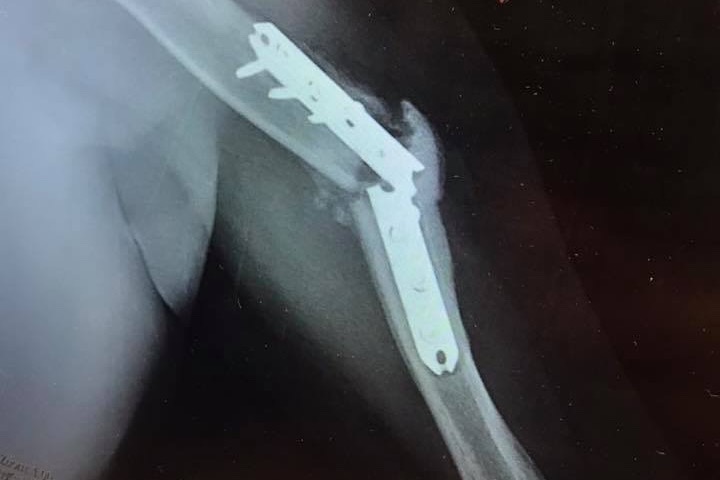

Brandon’s (dominant) arm did not heal correctly. The metals plates in his arm broke once, and broke again later that year; resulting in a second surgery to fix it. When recovering from this surgery he decided to try and go back to classes at Ohio State. However, it was still too soon and too much to try and take back on. The screws in his arm once again broke and he had to get a third surgery. That third surgery was June 5th, 2019. As of now; the third surgery looks promising. However, there are still many struggles. Six months out of surgery, and his doctor has said he will most likely not say he’s healed until two years down the road. Imagine all you’ve done in the past three years...I met my now husband, got married and have had my first child. In that same time period Brandon’s life has been put on pause as he’s been trying to recover. He puts on a good front, but the struggle behind closed doors has been very real and very hard and lonely. He has not been able to run for three years. He has not been able to use his dominant arm for three years. He is constantly being rejected for jobs due to his physical restrictions. Three years...and two more still ahead of him. Think about that.